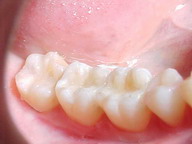

ANTES

INLAY / ONLAY

Restauração estética indireta* em resina